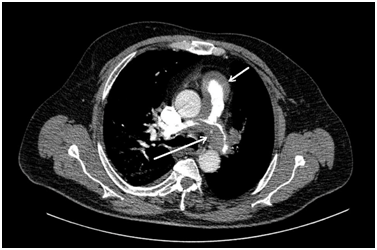

Analytically blood count and coagulation were normal, slightly elevated D-dimer 860 (mcg / L). In biochemistry highlighted a blood glucose 240 mg / dl, Reactive Protein C of 16.13 mg / L, with troponin T, CPK, renal function and normal liver. Gasometric had a PO2 of 50 mmHg, PCO2 of 33 mmHg and an oxygen saturation of 76%. Electrocardiography in sinus rhythm at 70 bpm with right bundle branch block and S1 Q3 T3. Given the marked hypoxemia and ECG data, is practiced appreciate a helical CT signs of pulmonary embolism (PE) in the trunk of the pulmonary artery and left main artery of the left upper lobe (Figure 1). Small right pleural effusion and dilated superior and inferior vena cava. There were signs of pulmonary hypertension (PH) and heart failure (RV / LV> 1), which confer poor prognosis. TTE was performed with 71% LV-EF, dilated right ventricle, severe pulmonary hypertension, moderate tricuspid insufficiency RV/RA gradient of 70 mmHg and severe pulmonary insufficiency and pulmonary artery flow with peak gradient of 40 through 19, with anatomy normal valve. Remains of thrombotic material in pulmonary tree. With the diagnosis of right heart failure secondary to pulmonary hypertension, anticoagulant and diuretic treatment begins with improvement. The study was completed with a lower limb doppler discarding thrombosis, abdominal ultrasound, where there are only simple renal cysts, prostatic hypertrophy and biliary sludge. The hypercoagulability study showed a hetererocigotic MTHFR C677T and S65C gene mutations with hyperhomocysteinemia, both with low prothrombotic relevance, we start treatment with folic acid. During the first weeks there is slight improvement, but after four months of adequate anticoagulation worsens with disabling dyspnea, increased edema, tendency to hypotension and presyncope episodes. It repeats the TTE where severe pulmonary hypertension persists with RV dilation of 68 mm, systolic dysfunction and septal flattening, by increasing pressures in right cavities. Tricuspid Insufficiency severe with PSP estimated of 75 mmHg.

Figure 1 The arrows point to the presence of  what looks like thrombotic material in the trunk of the pulmonary artery and left main artery of the left upper lobe.